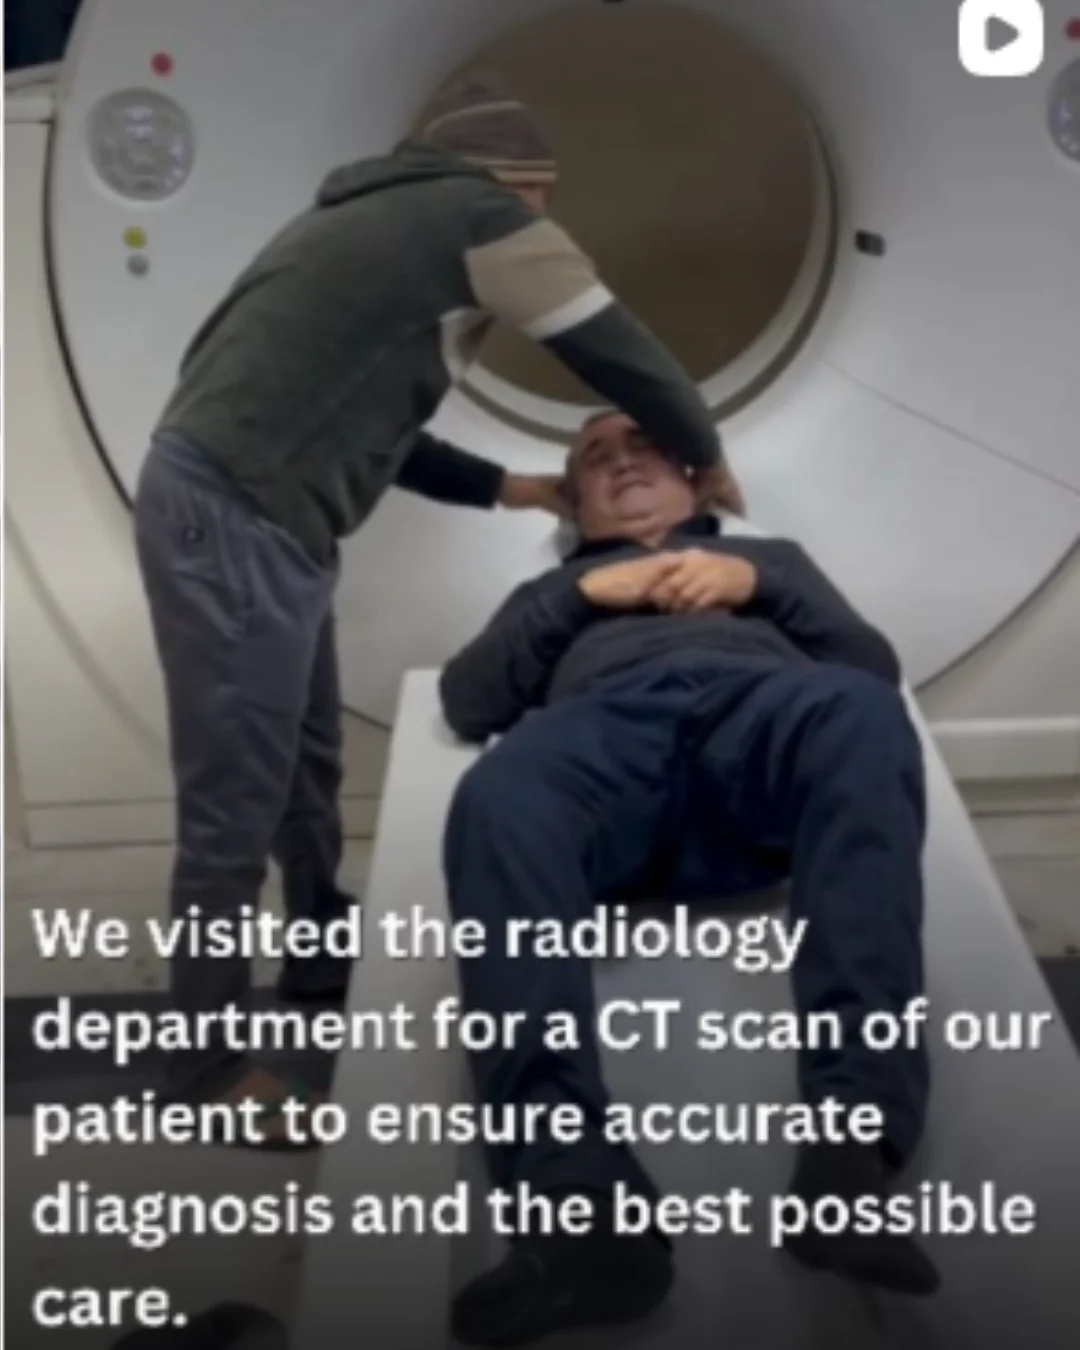

World-class hospitals, expert doctors, and modern treatment options with complete patient support.

From cardiology and oncology to transplants and surgery, care guided by experienced doctors.

Treatment coordination, hospital assistance, and recovery support — all managed by CURETAKE.